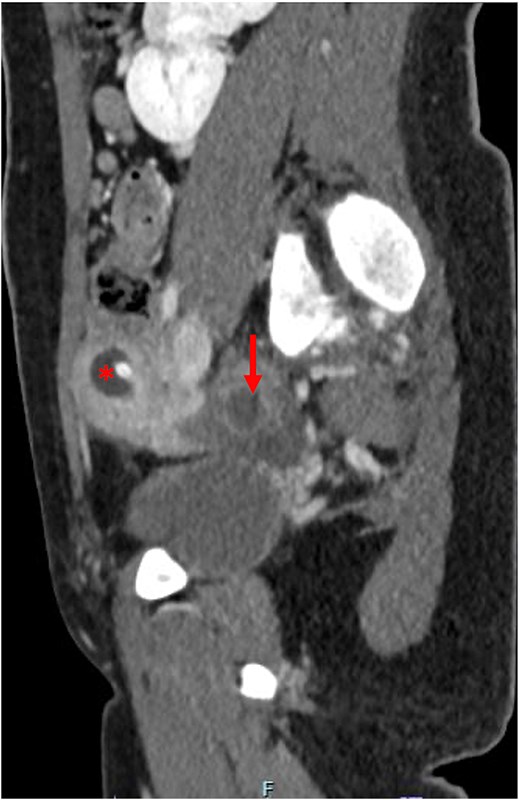

The patient was discharged on the second post-operative day with the uterine drain. She presented for follow-up 2 weeks later with complete resolution of pain. A CT AP showed resolution of the hematometra and interval improvement in the hematosalpinx (Fig. 3). The patient was instructed to perform vaginal self-dilation using the Frank method for eventual uterovaginal reconstruction, and weekly flushing of the uterine drain to prevent clogging [4]. A gynecology outpatient consult was placed for pharmacologic management of ovulation.

Post-operative computed tomography abdomen/pelvis demonstrating resolution of the hematometra (*) and improvement of the hematosalpinx (arrow).